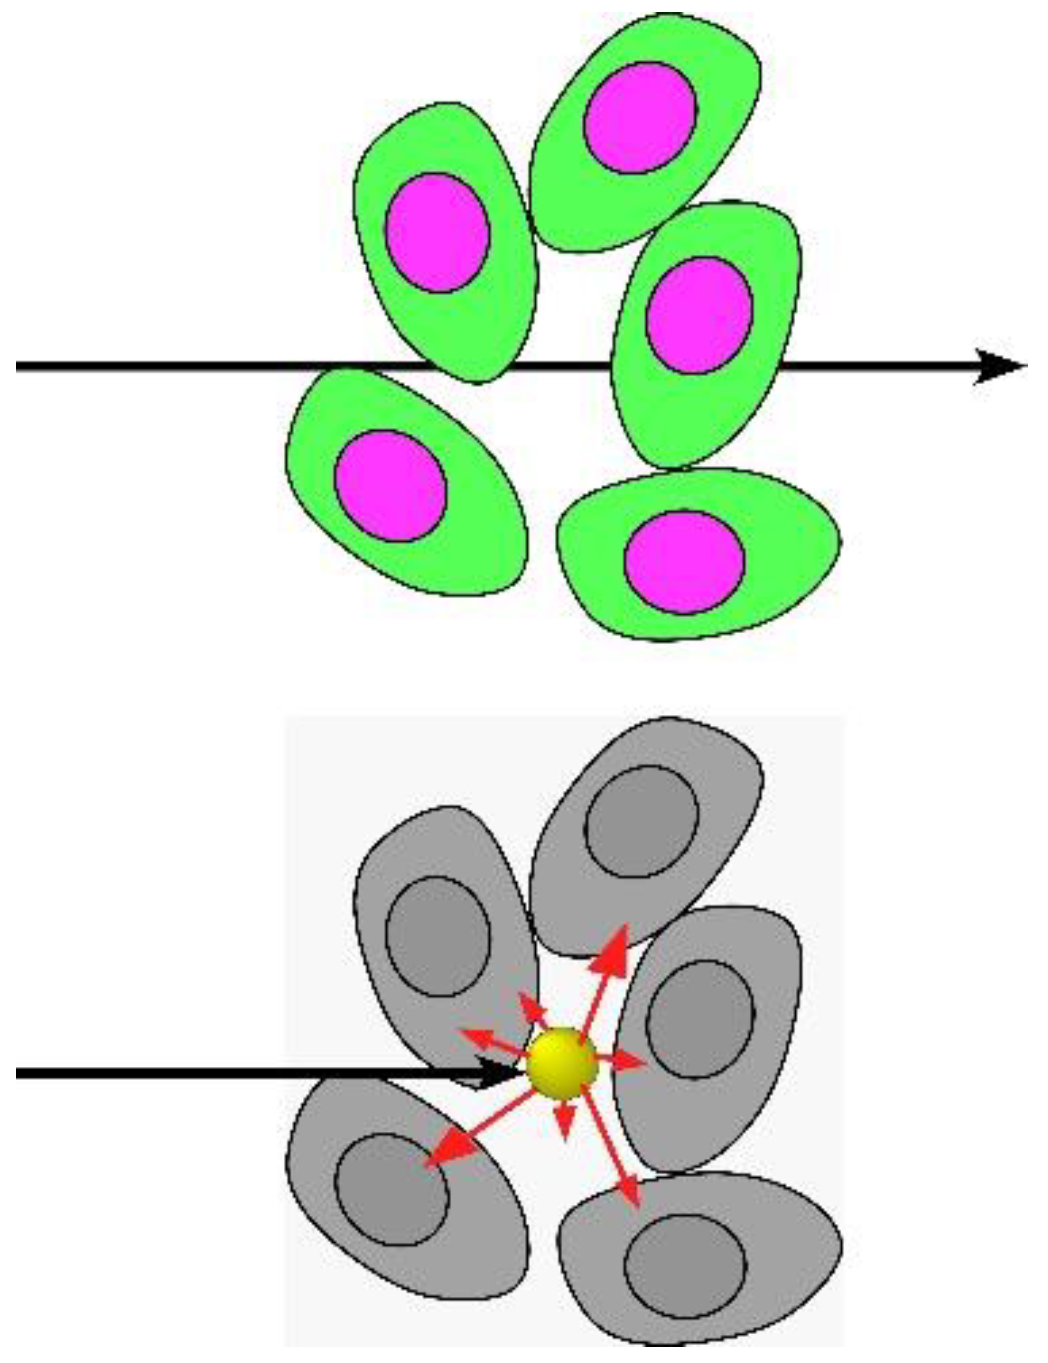

1.1. Mechanism

1.2. Gold Nanoparticle Imaging and Radiotherapy

1.3. Iodine Nanoparticles